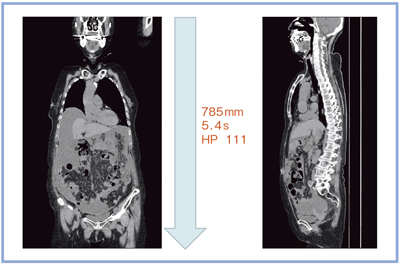

Aquilion PRIMEは開口径が780mmと広いため,高齢者など腕を上げられない患者さん,救急患者さん,挿管されている患者さんなどでも,セッティングがしやすい。また,年々増加の一途を辿っている高齢者は撮影時の息止めが難しいが,Aquilion PRIMEでは,785mmをヘリカルピッチ(HP)111で5.4秒で撮ることができる(図6)。

図6 ウルトラヘリカルスキャン(AIDR 3D:Mild)